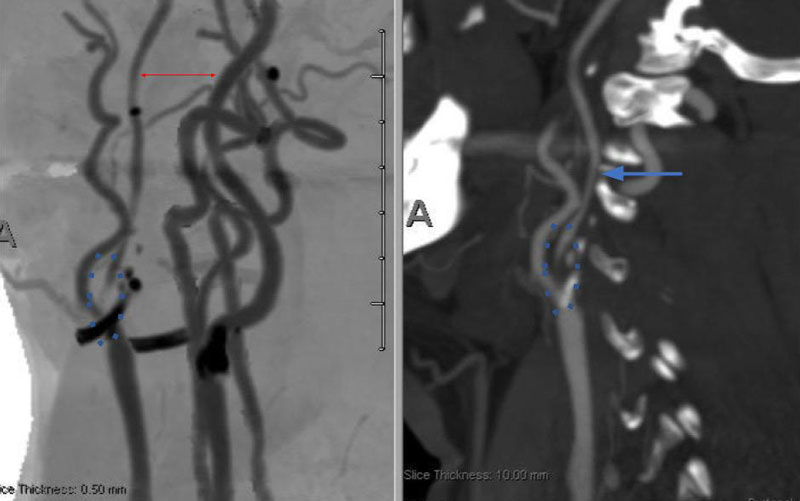

CT Brain Perfusion Imaging confirmed marked delay in contrast/blood Time to Peak (TMax) and Mean Transit Time (MTT) with decreased right hemispheric Cerebral Blood Flow and elevated Cerebral Blood Volume. These findings suggested that this critical right ICA stenosis resulted in significant hemodynamic perfusion failure and ischemia within the right hemispheric territories of the right MCA and ACA vascular distributions (Figure 2). No large vessel intracranial occlusion requiring emergent thrombectomy was observed, and the mild initial symptomatic presentation favored further imaging and medical optimization prior to revascularization attempts.

Figure 2. A) CT Brain Prefusion Tmax confirms delayed flow; B) MTT, CBF, CBV and Hybrid Threshold Parametric Maps of Right MCA/ACA revealing diminished CBF, elevated CBV, and prolonged MTT of at-risk Ischemic Tissue.